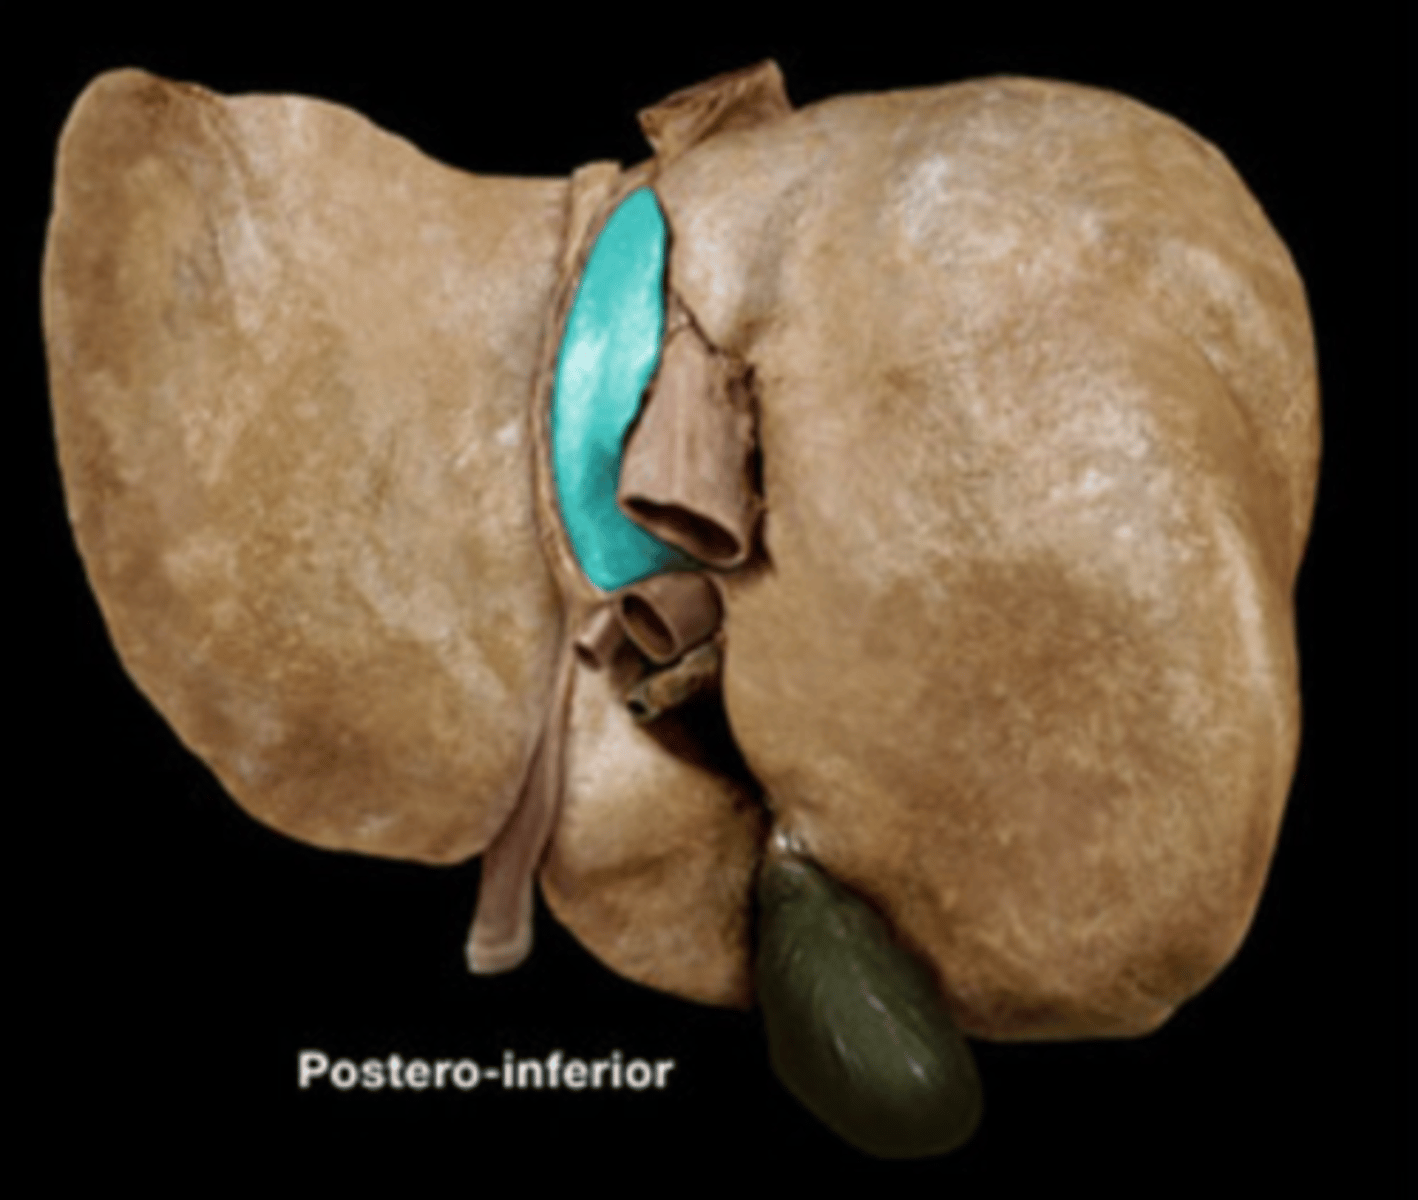

Caudate Lobe of Liver

Quadrate Lobe of Liver

Falciform Ligament

Ligamentum Teres

Gall Bladder